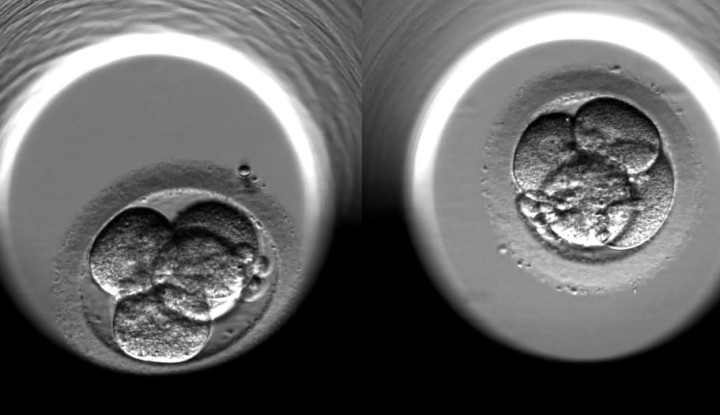

De a tapasztalatok szerint nagyon sok páciens egyáltalán nem szeretné sem az embrióit, sem a kezelését a magyar államra bízni.

A cseh és a szlovák meddőségi centrumokban eddig sem voltak ismeretlenek a magyar párok, mióta azonban a kormány egy értelmetlen magyarázatra hivatkozva gyakorlatilag betiltotta a magán meddőségi klinikák működését itthon, megindult a dömping. Az, hogy itthon bizonyos eljárások elérhetetlenek voltak már eddig is, egy dolog. De a tapasztalatok szerint nagyon sok páciens egyáltalán nem szeretné sem az embrióit, sem a kezelését a magyar államra bízni. Délelőtti hírösszefoglaló. Ha érdekel a téma, akkor ezt a cikket olvasd el.